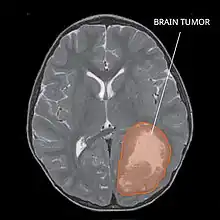

| Primitive neuroectodermal tumor of the central nervous system in a 5-year-old |

The rate of PNETs in not correlated with sex, but it shows a correlation with age.[1] Most cases occur in children around 5 years of age, having a very low frequency in adults.[1] Regarding genetic mutations, a specific type of gene alteration that directly leads to this tumor hasn't been defined yet.[1] However, a positive correlation between individuals with Li-Fraumeni syndrome with a mutation in the gene p53 and PNET has been reported.[2] A significant number of individuals with mutations on the rb tumor suppressor gene have also developed the tumor.[2] Such gene encodes for the protein Rb responsible for stopping the cell cycle at the G1 phase.[6] Another possible contributing factor are mutations in the CREB-binding protein, whose function includes activating transcription,[6] but this interaction still need to be studied further.[2] It has also been presumed that the tumor can arise from cranial irradiation.[2]